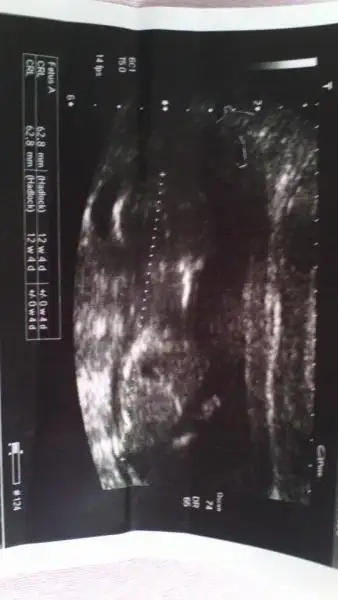

Eki Görüntüle 473829 bu bir erkek bebek genital nub cikintisi gayet yukarda